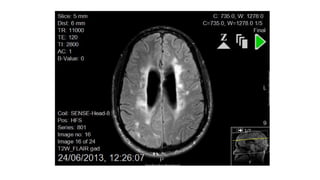

T2 imaging – axial / transverse plane

Flair images – axial / transverse plane